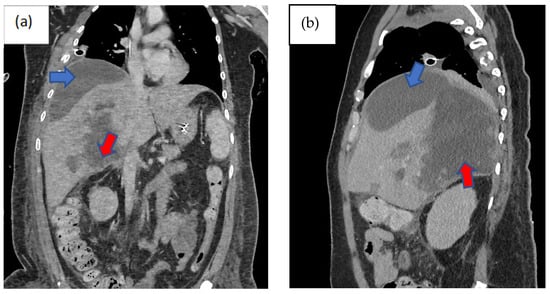

Three days following the laparotomy, the patient developed ventilator-associated pneumonia and intra-abdominal sepsis and was treated empirically with fluconazole and piperacillin–tazobactam. Repeated imaging of the abdomen was carried out in view of a poor response to antimicrobial therapy and showed the formation of biloma (Figure 1). A percutaneous subdiaphragmatic drain was inserted under computed tomography (CT) guidance by the interventional radiology team to facilitate drainage, despite being able to drain only a minimal amount, and the drain was dislodged after three days. In view of ineffective percutaneous drainage with worsening intrabdominal sepsis despite one week of adequate antimicrobial therapy, upon discussion with the hepatobiliary team, we decided to proceed with a hemi-hepatectomy for the removal of the biloma.

Figure 1.

Computed tomography scan of the abdomen non-contrasted phase showing heterogenous areas consisting of hematoma and laceration at segments V, VI, VII, and VIII extending down to the subhepatic region (red arrow). Inferiorly, it extends down to the hepatic flexure, just lateral to the right pararenal space. Another subcapsular collection was seen adjacent to right liver lobe (blue arrow): (a) coronal view, (b) sagittal view, and (c) axial view, with findings as aforementioned.

Imaging remains the gold standard for diagnosing bilomas, with ultrasound (US) often being the initial imaging modality used. Bilomas typically appear as well-defined hypoechoic fluid collections within the abdomen that vary in size and shape, ranging from small localized areas to larger, more extensive masses. It also has the capability of detecting the content within the biloma by showing a variety of findings ranging from well-defined collections in the liver parenchyma to extensive fluid collections across the abdomen [8]. Notably, US findings show heavily loculated bilomas are often linked to infection [9]. CT imaging can help identify the overall structure of the biloma, delineating clear margins that can be either encapsulated or non-encapsulated [10]. While CT imaging offers a more intricate view of bilomas, it lacks the capability to conclusively distinguish among various potential diagnoses, including seroma, abscess, lymphocele, liver cyst, hematoma, and pseudocyst [11]. Consequently, additional imaging modalities such as magnetic resonance (MR) imaging or hepatobiliary cholescintigraphy may be necessary to help validate the diagnosis. Direct sampling of the biloma together with these imaging techniques will also help with the diagnosis [10]. In T1-weighted images, bilomas will display low signal intensity, whereas in T2-weighted images, high signal intensity is seen [12]. Furthermore, MR imaging can help to define the characteristics of a biloma. While contrast infrequently penetrates the biloma, rim enhancement and septations occasionally occur due to reactive inflammation and infection [12]. Hepatobiliary cholescintigraphy serves as a highly efficient non-invasive imaging technique for diagnosing and strategizing treatment for bilomas by utilizing a radiotracer known as Tc-99m iminodiacetic acid, which is commonly referred to as hepatobiliary iminodiacetic acid (HIDA) imaging [10,13]. HIDA imaging exhibits a high level of sensitivity in detecting bile leaks [13]. Nonetheless, it lacks the ability to offer detailed imaging of the surrounding anatomical structures. Single positron emission computed tomography (SPECT) is another imaging technique that has the ability to furnish more intricate imaging of potential leak locations, proving particularly valuable in planning percutaneous image-guided drains [10]. Endoscopic retrograde cholangiopancreatography (ERCP) and percutaneous transhepatic cholangiogram (PTC) can be considered not only for diagnostic tests but also may offer some degree of intervention either percutaneously or endoscopically [13]. Other minimally invasive investigations available are CT-guided sampling technique and US-guided sampling technique. However, these techniques require laboratory assistance to analyse the sample collected [10]. In our case, CT imaging was sufficient to give us the information we need. The initial CT imaging (Figure 1) revealed a rim-enhancing lesion surrounding the biloma, suggesting a potential infective biloma. However, we did not perform a biopsy and or staining hepatic tissue during the hemi-hepatectomy to definitely confirm that Rhodotorula mucilaginosa originated from the biloma itself. This limitation underscores a key aspect of our study, highlighting the need for further investigations to establish a direct link between the presence of Rhodotorula mucilaginosa and the biloma. MR imaging was not performed in this patient which shows another limitation in this case. MR imaging might indicate presence of septations within the biloma and this might be the reason why percutaneous drainage failed in this patient.